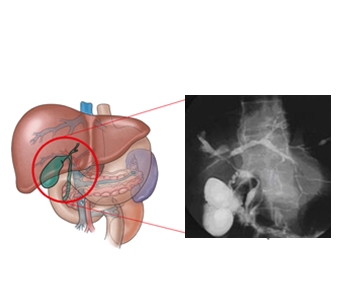

간문부 담관암(Klatskin's tumor)

담석

경화성 담관염

총담관 담석

총담관 낭

궤양성 대장염

간디스토마